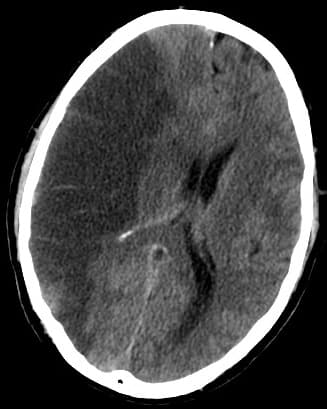

Un accident vasculaire cérébral (AVC), anciennement accident cérébrovasculaire (ACV) et populairement appelé attaque cérébrale, infarctus cérébral ou congestion cérébrale (AVC et ACV étant tous deux des terminologies acceptées), est un déficit neurologique soudain d'origine vasculaire causé par un infarctus ou une hémorragie au niveau du cerveau. Le terme souligne l'aspect soudain ou brutal des symptômes, mais dans la plupart des cas les causes de cette affection sont internes (liées à l'âge, l'alimentation ou l'hygiène de vie, notamment). Les symptômes varient beaucoup d'un cas à l'autre selon la nature de l'AVC (ischémique ou hémorragique), l'endroit et la taille de la lésion cérébrale : aucun signe remarquable, perte de la motricité, perte de la sensibilité, trouble du langage, perte de la vue, perte de connaissance, décès. Les symptômes sont brutaux : ils apparaissent en quelques secondes. Ils peuvent disparaître assez rapidement ; s'ils disparaissent dans l'heure on parle d'AIT, s'ils perdurent plus d'une heure on parle d'AIC. En cas de survie, le processus de récupération (encore mal compris) passe par une phase de récupération spontanée durant de quelques semaines à quelques mois, suivie d'une période d'évolution plus lente, de plusieurs années. Dans les pays occidentaux un individu sur 200 est atteint d'un accident vasculaire cérébral chaque année. En France en 2019, on dénombre chaque année plus de d’accidents vasculaires cérébraux, soit un toutes les quatre minutes selon l'INSERM. 80 % de ces cas sont des ischémies et 20 % des hémorragies. La probabilité d'AVC ischémique augmente avec l'âge, tandis que la probabilité de faire un AVC hémorragique . L'AVC est moins souvent mortel (passé de la seconde à troisième ou quatrième cause de décès dans la plupart des pays occidentaux)) grâce aux progrès de la médecine, mais il y est devenu la première cause de handicap physique de l'adulte, en raison d'un taux de survie amélioré, mais d'une récupération difficile des fonctions cérébrales lésées.